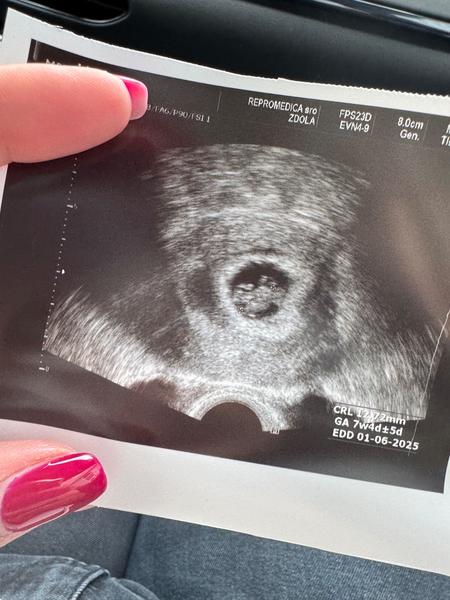

@babushkaem už dostanes aj knižku ? … ja som teraz 10+5 ale na kontrolu k svojej gyn idem až 12.11. Ale idem na skrining prvý 8.11. Do centra tak dúfam a modlim sa že bude všetko ok lebo nasposledy som bola u mojej dr keď som bola 7tt tak už mám nervy

@nikuska5322 no hej da, ja som doteraz chodila na kontrolu kazdy tyzden, teraz idem prvy mrat po dvoch tyzdnoch a uz mam nervy. To tak dlho ako ty ani neviem co by som robila 🤣 a uz minule mi brala krv na knizku, to mam prist na kontrolu kvoli hematomu, a o dalsie dva tyzdne 21.11 na skrining. Mna centrum pistilo po ukoncenim 7tt ze mam ist k svojej gynekologicke

@babushkaem ja som bola naposledy v centre keď mi vlastne určili akciu srdiečka potom hneď na to som bola u svojej gyn a zatiaľ som aj mala objednat má skrining a robia hi aj v heliose tak som sa tam objednala rovno a to idem 8.11. Ale mám hrozne nervy že či je všetko ok a tak ale tak dúfam že je … a k svojej gyn idem 12.11. A to mi dá knižku zoberie krv a tak no len dúfam že sa dovtedy nezblaznim 😅

@nikuska5322 ja uz mám hemotom preč, videla som už aj pohyby, budúci štvrtok idem na 1 velke sono a trisomy testy. Dúfam, že bude všetko ok. A lieky akurát vysádzam, aj progesteron, aj medrol, aj estrofem. Ostane mi vlastne clexan a aj to idem k hematologicke, ci este treba. Inak nic. Uz ani nejak priznaky extra nemám. A ty co?

@babushkaem ja už som bola aj na veľkom sone prvom bolo všetko ok babo rastie pekne akurát včera som si bola aj u svojej gyn po knižku a brali mi krv na trisomy testy tiež aj EKG som bola malé zase bolo o niečo väčšie než v piatok tak dúfam že aj naďalej bude všetko ok 😊